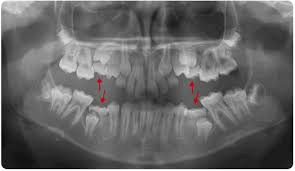

Ankylosis Primary Second Molars Teeth Treatment Teeth Orthodontics